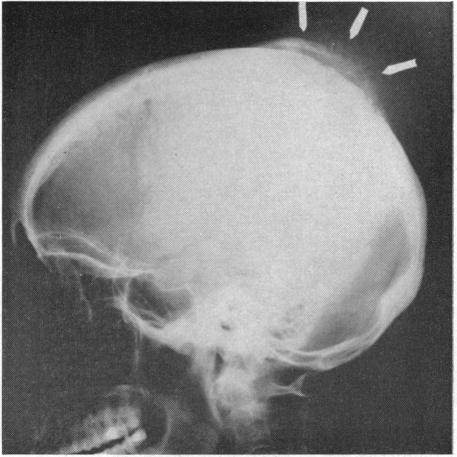

A clinico-pathologic recapitulation of experiences with a variety of masses which are visible and palpable and involve the cranium has led to the realization that examples of almost every major category of disease may be encountered. A review of the many varieties broadens our perspective of the diagnostic possibilities when confronted with a new case. The apparently innocent nature of scalp masses may be misleading, and this review can assist in alerting us to the need for stepwise investigation in tracking down the extent of involvement, especially intracranially. The use of limited office surgical procedures should be reserved for the simplest sebaceous cysts and other, readily identifiable, masses entirely limited to the scalp. The midline mass, in particular, deserves respect for its possible continuity with meninges or neural tissue. It should be remembered that the cranial mass may also be a manifestation of more widespread disease processes.